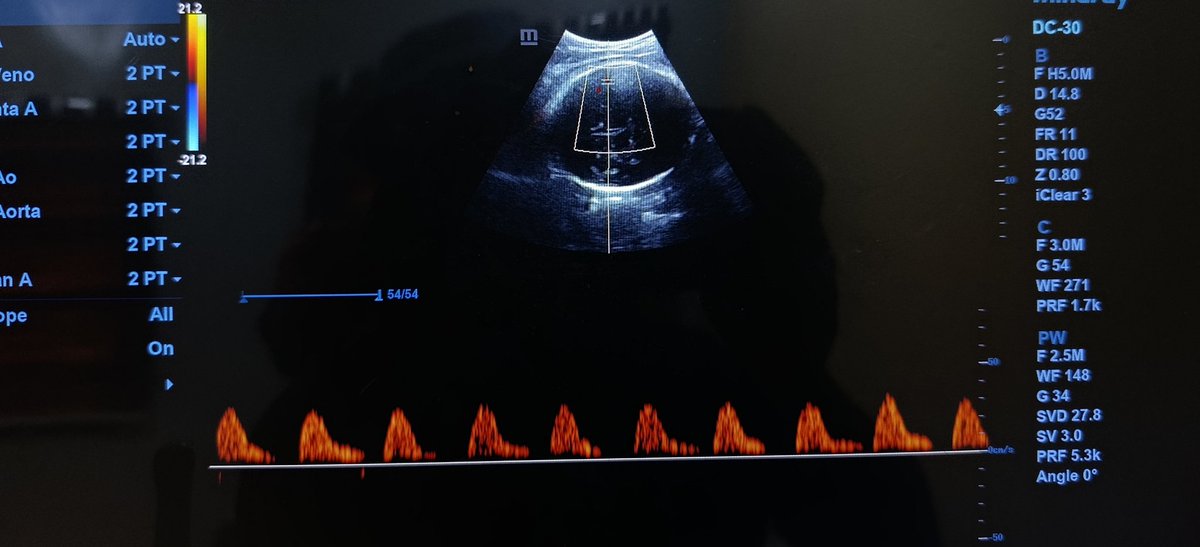

@popoolaadaniel First image: reversed end diastolic flow: ?iugr second: absent end diastolic flow: ? Placental insufficiency or issues Third image: normal sharp systolic forward flow followed by normal end diastolic flow just inverted